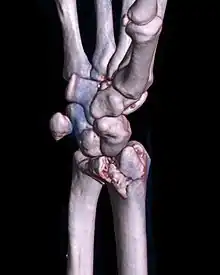

| A palmar Barton's fracture of the right wrist, as shown on a 3D-rendered CT scan | |

There exist two types of Barton's fracture – dorsal[3] and palmar, the latter being more common. The Barton's fracture is caused by a fall on an extended and pronated wrist increasing carpal compression force on the dorsal rim. Intra-articular component distinguishes this fracture from a Smith's or a Colles' fracture. Treatment of this fracture is usually done by open reduction and internal fixation with a plate and screws, but occasionally the fracture can be treated conservatively.[4]